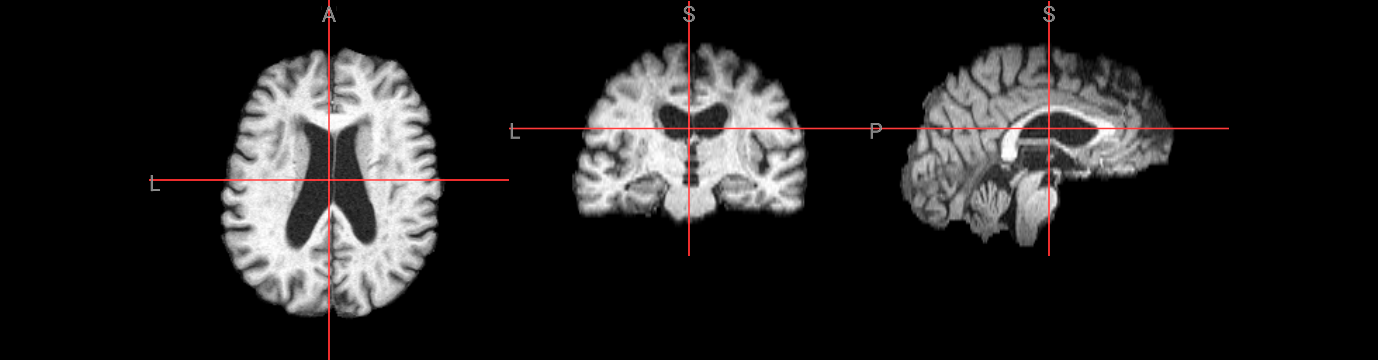

Brain extraction is a fundamental preprocessing step in neuroimaging analysis, particularly critical for structural image segmentation where precision matters most. While BET is straightforward to use, achieving optimal results often requires understanding how to fine-tune parameters for challenging datasets. This interactive version covers the core BET fundamentals, including parameter adjustment techniques for difficult images, and troubleshooting approaches for problematic cases. The hands-on format allows you to experiment with different settings and immediately see their effects on brain extraction quality.